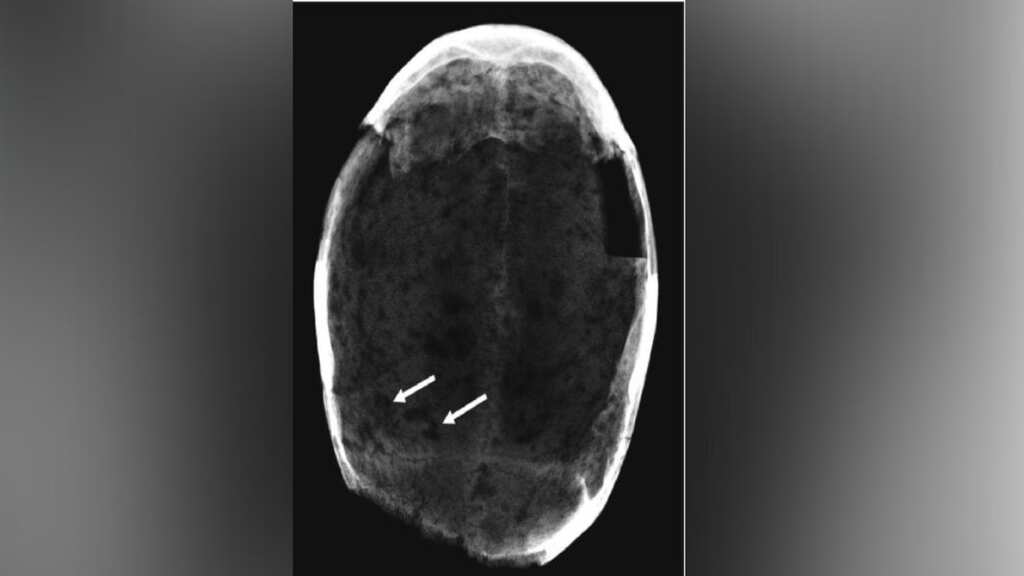

Were Italians consuming cocaine in 17th century to curb hunger and thirst? Study says...